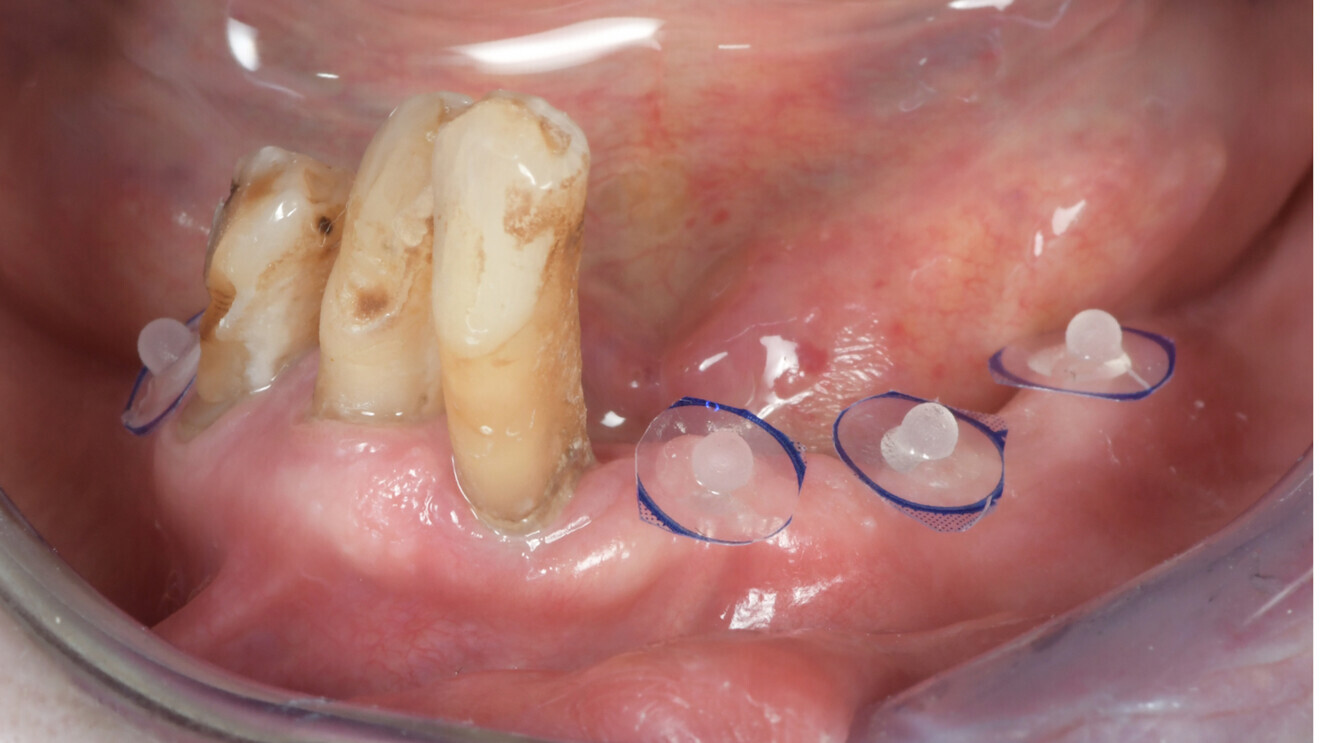

La combinaison des données DICOM et STL dans le cadre de l’édenté complet ou subtotal est rendu compliquée par le manque de repères fiables et fixes. L’astuce, ici, est de coller des autocollants avec des billes radio-opaques (www.suremark.com). Ces billes seront identifiées tant au niveau de la radiologie par leur opacité que sur l’empreinte optique par leur volume. La combinaison des données est alors facilitée (Fig. 5). Lors de la planification du traitement implantaire, le logiciel DTX Studio Implant a été utilisé (Fig. 6). Il a été décidé de placer quatre implants.

Fig. 5 : Vue intra-orale de la mandibule montrant l’édentement partiel et des autocollants avec des billes radio-paques.